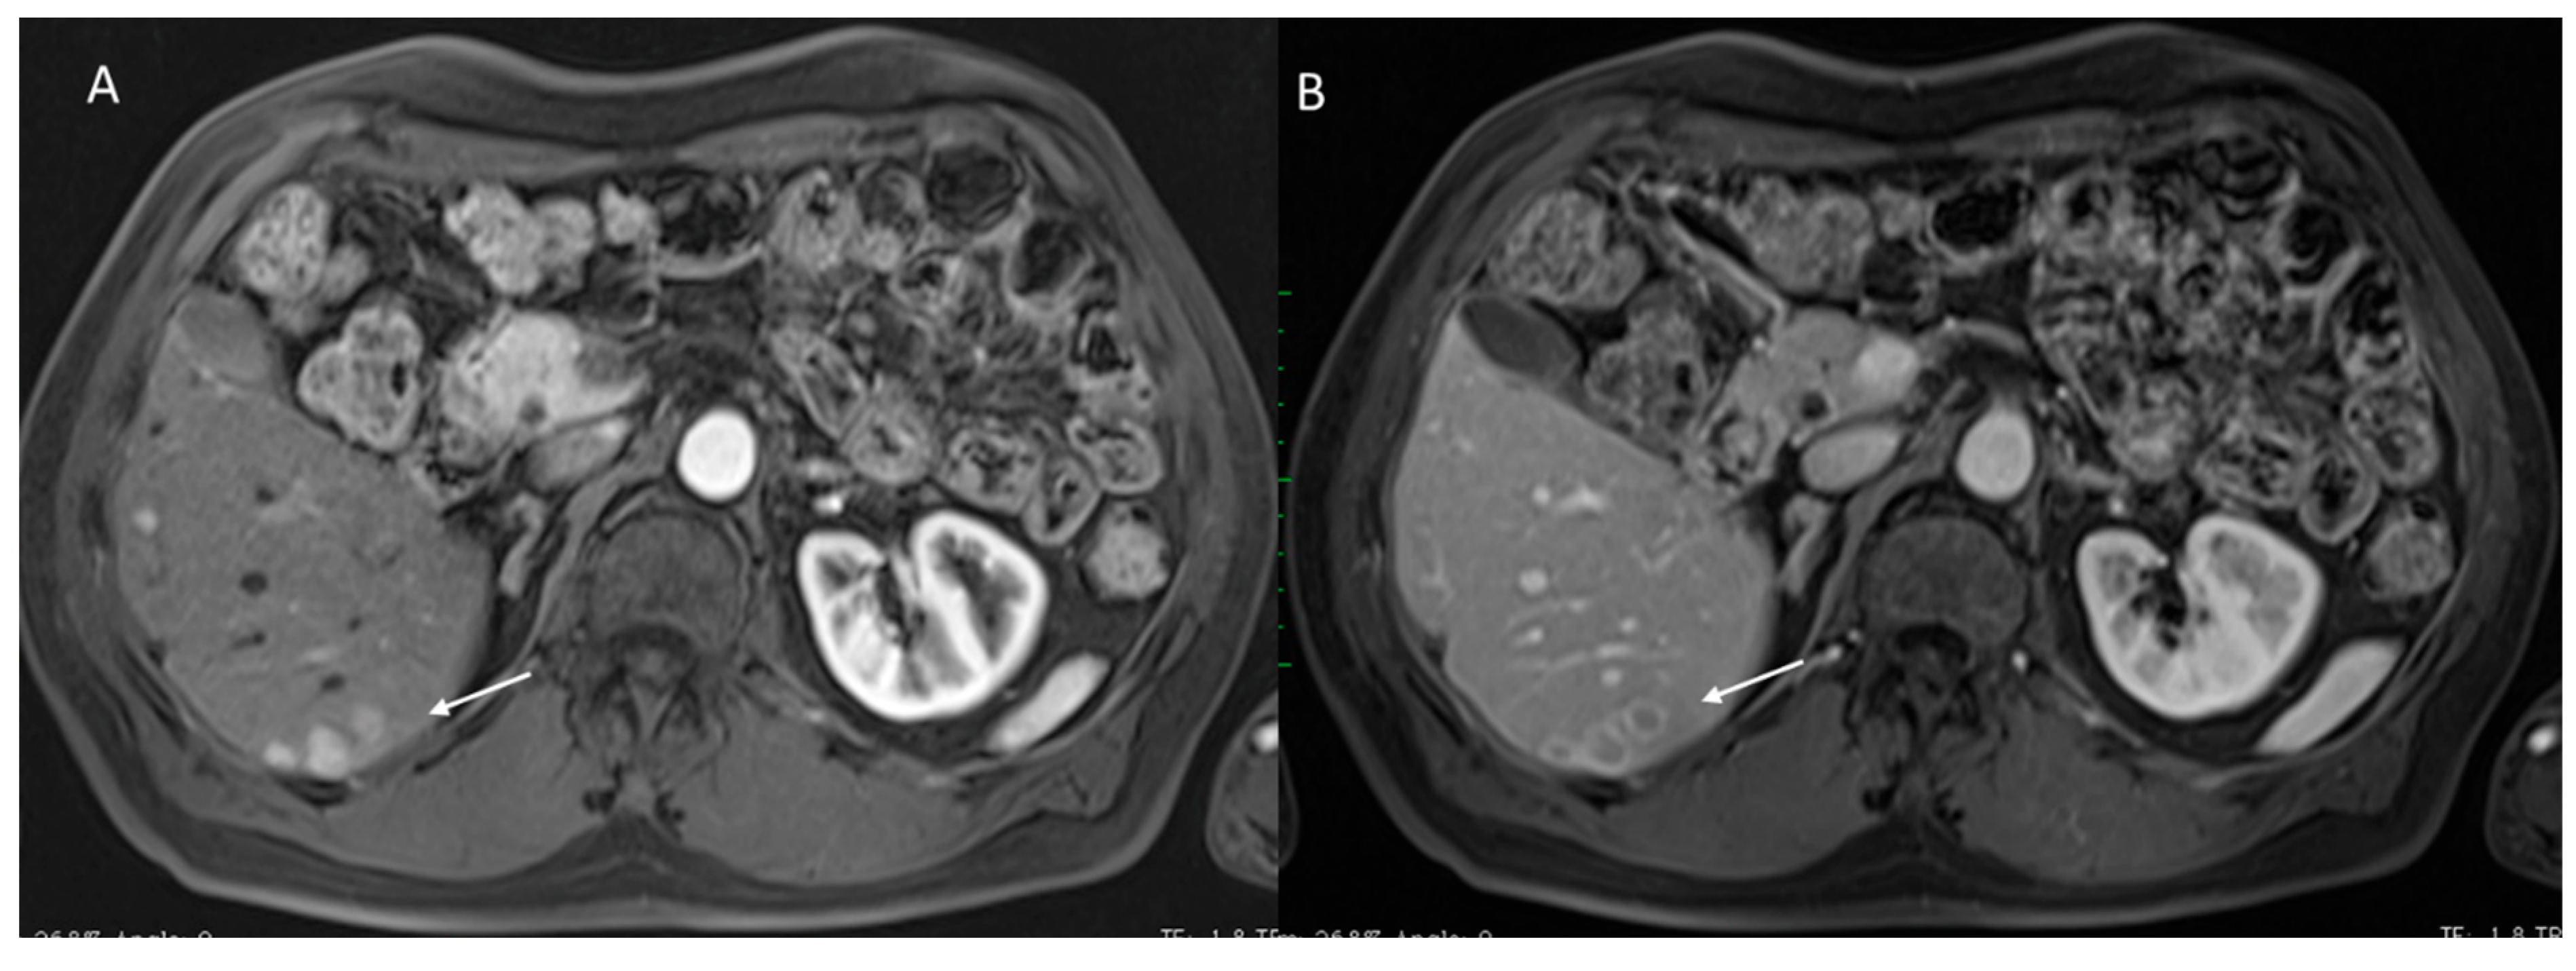

2.3. CEUS-LI-RADS

2.3.2. CEUS-LI-RADS Categories

2.3.3. CEUS-LI-RADS vs. CT/MRI LI-RADS